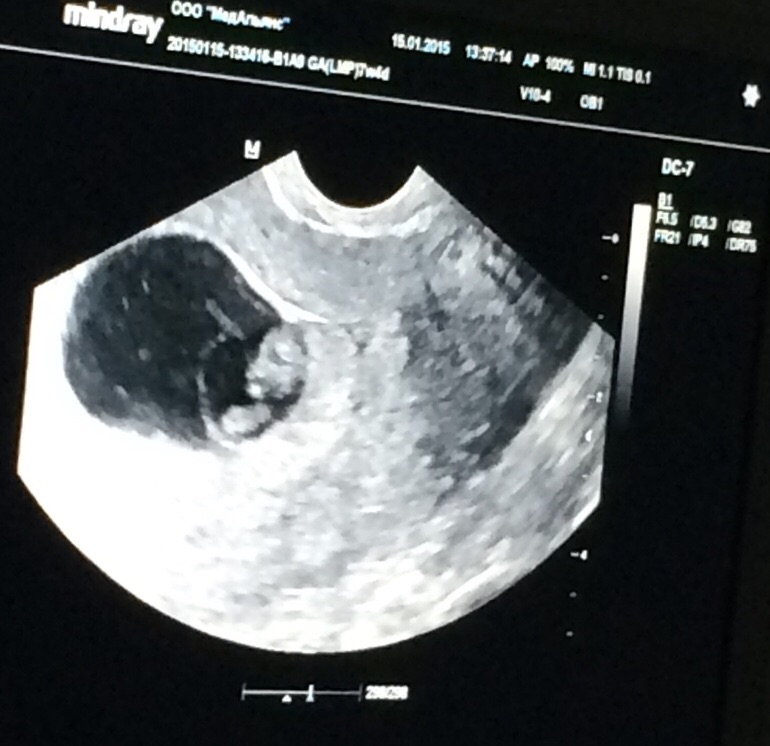

Результаты: УЗИ, КТГ, доплера, скринингаДевочки, понимаю, что тут не специалисты, но посмотрите, пожалуйста, снимок узи.. Как думаете? Может помните своих малышей на этом сроке.

7-8 недель, пя одно

А мне кажется два. Если один, то второе поменьше как будто голова. Но я помню у меня в 7 недель как креветочка был, там голову не отличишь от тела.

А я два вижу,один чуть выше,а другой чуть ниже и меньше,или то один и выше это головка малыша.Правда пишут,сердцебияния должны были два услышать.Двойня это супер))

Один. А вообще Вам по сердцебиению сказать должны были. Если эмбрионов два, то серцебиений тоже два :)

На фото видно 1. Но они могли сфокусироваться только на 1-м плодном яйце для этого фото, а второе в это время было вне фокуса, на втором плане как бы. Говорят не по картинке :) А по сердцебиению: 1 или 2. И при узи сканят всю полость матки, а картинка может быть только с одной ее части :) Я бы поверила на Вашем месте.

Этот снимок, где врач узист, сказала, что видно двоих. Вчера мельком посмотрели в жк, сказали два сердцебиения, но больше ничего не смотрели. Сделала узи сегодня, но врача сразу предупредила.. А теперь сомневаюсь.. Не знаю, почему-то не верится..

Два сердцебиения не должно вызывать сомнений. Да и плодное яйцо как на 8 недель большое. Вполне вероятно